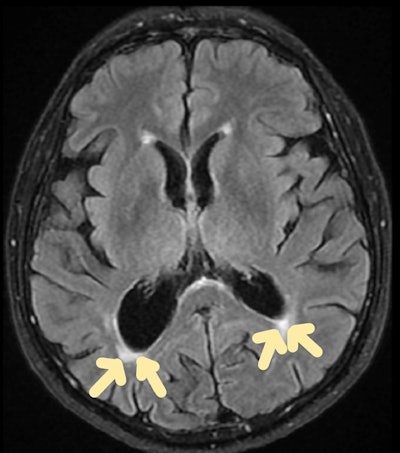

Carbon monoxide poisoning. Brain MRI scan (axial FLAIR sequence) shows periventricular hyperintensities. All images courtesy of Dr Gurubharath Ilangovan et al and the ESR's EPOS database.

Carbon monoxide (CO) poisoning

CO poisoning can have an impact on the central nervous system and the cardiovascular system. Neurological symptoms resulting from acute CO poisoning range from a minor headache to a coma and possibly death. For most patients, these symptoms can be alleviated with oxygen inhalation or hyperbaric oxygenation. Even a year after CO poisoning, very few people experience long-term neurological symptoms as a result of delayed encephalopathy.

Carbon monoxide poisoning. Brain MRI scan (coronal FLAIR sequence) shows symmetric hyperintense foci in the globus pallidus.

Acute CO poisoning should be diagnosed and detected as soon as possible. In the absence of a history of CO exposure, early detection and diagnosis of CO poisoning can be challenging due to a lack of pathognomonic signs or symptoms.

"The delayed symptoms of CO poisoning result from the inhibition of the mitochondrial electron transport enzyme system by CO and the activation of polymorphonuclear leukocytes, which produce brain lipid peroxidation and diapedesis," the authors wrote.

In these patients, CT shows low attenuation in the globus pallidus. On MRI, the medial portions of the globus pallidus appear as bilateral areas of low signal intensity on T1-weighted images and of high signal intensity on T2-weighted and FLAIR images. The degree of carboxyhemoglobin and the range or intensity of MRI results do not appear to be related.